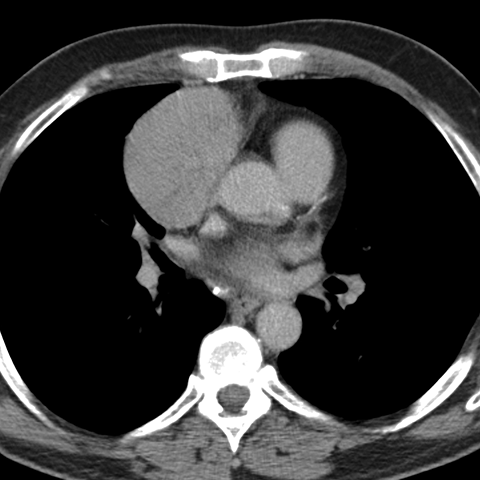

Mediastinal mass, thymoma [3 of 3]